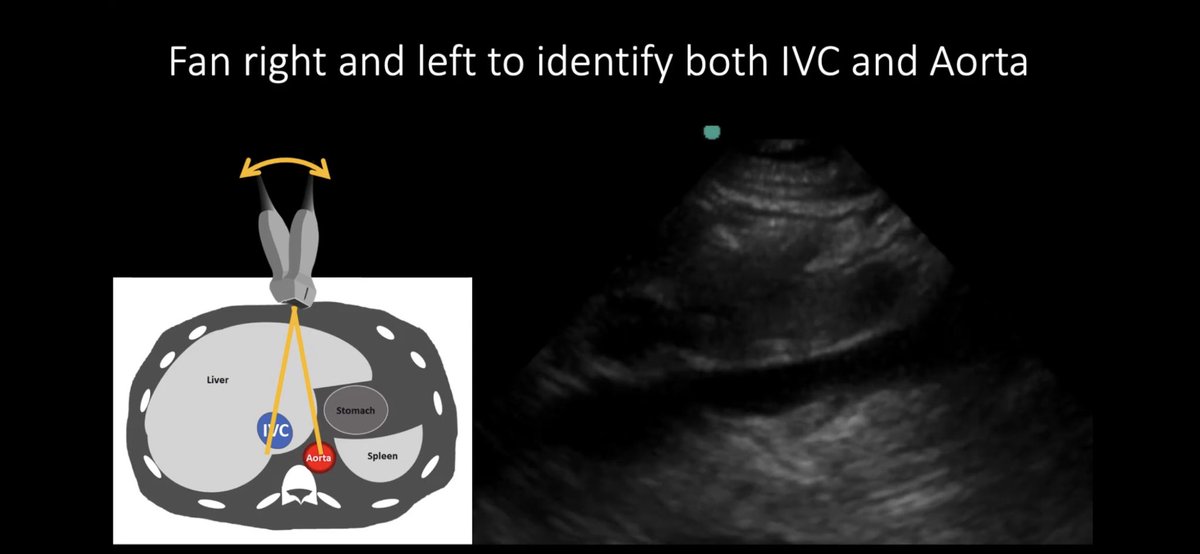

How? Rock the probe (phased array w/ indicator pointing cranially) just below xiphoid (midline). You will be between aorta and IVC. Try to identify Ao first (more medial) and than fan the probe laterally and you will see IVC.

How? Probe movements 🤚

⚠️For IVC US you will need to know how to rock and do fanning. Rock to find RA! Fan the probe more laterally so you can identify IVC! After that sweep the probe so you can be perpendicular to the UVC.